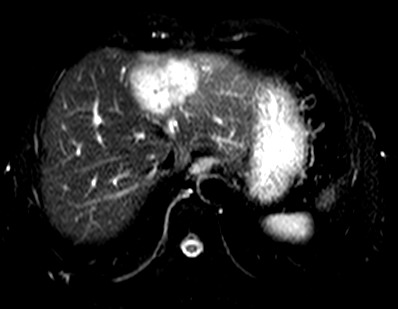

标题: CT19720:肝右叶血管瘤。肝左叶内侧段病灶考虑什么? [打印本页]

标题: CT19720:肝右叶血管瘤。肝左叶内侧段病灶考虑什么?

男,48岁,肝区不适月余,伴隐痛。

支持右叶血管瘤,左叶病灶考虑肝腺瘤。

1)不排除肝左叶肝癌。2)肝右叶血管瘤。

肝左叶炎性病变,肝癌待排。2)肝右叶血管瘤。

1.肝右叶血管瘤;2.肝左叶炎性假瘤?肝癌?建议穿刺活检.

右叶病灶典型,左叶病变慢性炎块

1、肝右叶血管瘤(典型)。

2、肝左叶病灶,强化不明显,疑炎性假瘤,建议结合临床并密切随访。

1、肝左叶炎性病变,肝癌待排。

2、肝右叶血管瘤。

肝左叶脓肿,肝癌待排。2)肝右叶血管瘤